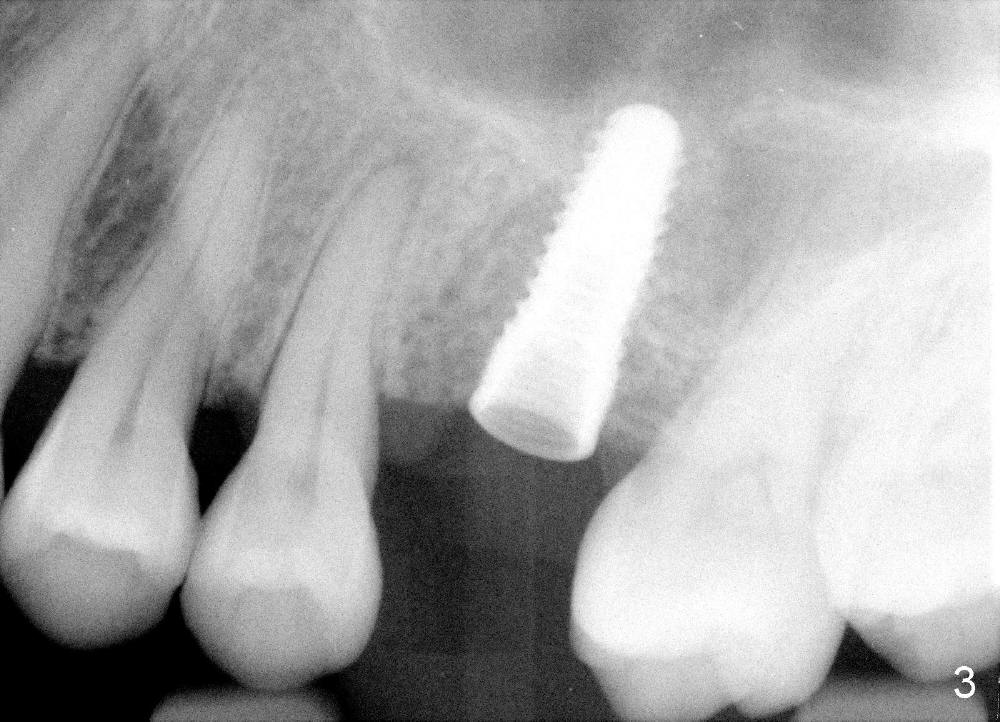

After local anestheisa, an incision is made. The initial osteotomy at the site of the upper left 1st molar is created by 1.6 mm pilot drill at the depth of 6 mm (Fig.1), followed by insertion of bone expanders 2.6, 3.0, and 3.4 mm at approximately 7, 8, and 9 mm deep (Fig.2). A 4.1 mm bone tap is inserted approximately 10 mm without much binding. Mineralized allograft mixed with Osteogen is used for sinus lift. A 4.5x12 mm implant is placed with insertion torque around 35 Ncm (Fig.3). A 5.2 mm healing abutment is placed. The flaps are sutured. The wound is covered by perio dressing.